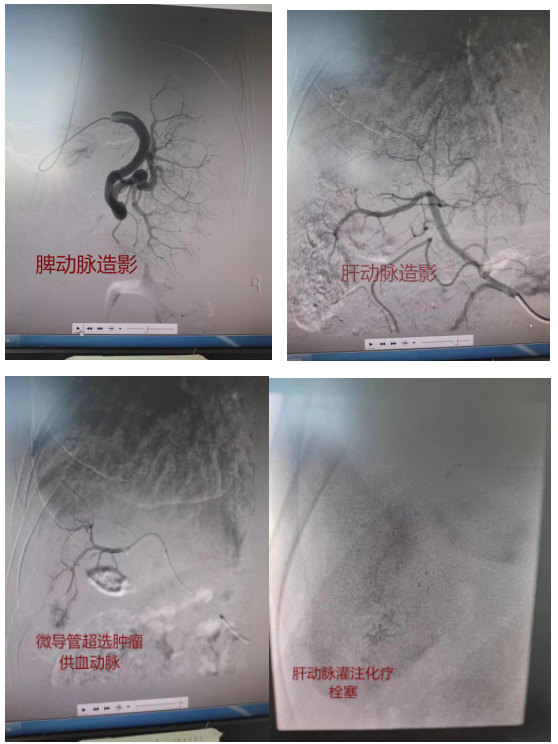

肝动脉化疗栓塞术(TACE)是肝癌介入治疗的一种,通常是指在患者大腿根部的股动脉进行穿刺,将细微的导管穿入,通过数字减影血管造影机(DSA)的透视引导,将导管送至肝内肿瘤部位,医生将抗癌药物、栓塞剂通过导管注入肝内肿瘤动脉的一种治疗方式。

肝动脉化疗栓塞术(TACE)不但可以直接杀死肿瘤细胞,而且还能阻断肿瘤血供,使得肿瘤没有营养而"饿死",是目前中晚期肝癌国内外公认的首选治疗方法。由于穿刺股动脉患者术后通常需要卧床24小时,我科在郎根主任医师带领下改变以往术式,改为穿刺桡动脉,患者术后,可正常下床活动,只需要腕部腕带加压即可,为需要手术患者术后带来了极大方便,类似我们也开展了经桡动脉全脑血管造影,以及脾动脉栓塞,子宫肌瘤子宫动脉栓塞等手术,通过改变穿刺位置,为患者最大程度减轻痛苦!